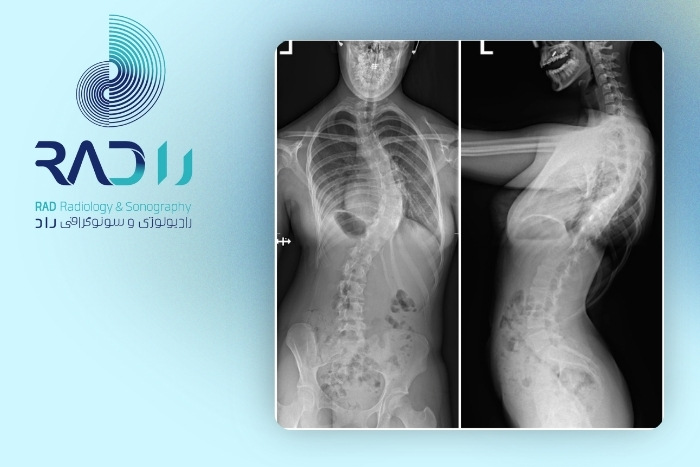

دقت رادیوگرافی ستون فقرات در تشخیص اسکولیوز

رادیوگرافی ستون فقرات (X-ray) استاندارد طلایی (Gold Standard) در تشخیص و ارزیابی اسکولیوز محسوب میشود. دلیل این موضوع توانایی بالای رادیوگرافی در نمایش انحرافات استخوانی، میزان چرخش مهرهها و اندازهگیری دقیق زاویه انحراف ستون فقرات است.

اسکولیوز بهطور علمی زمانی تشخیص داده میشود که زاویه Cobb برابر یا بیش از ۱۰ درجه باشد.رادیولوژی میتواند انحرافهای بسیار خفیف (حتی نزدیک به ۵–۷ درجه) را نیز نشان دهد اما تشخیص قطعی از ۱۰ درجه به بالا انجام میشود.

از نظر تشخیص وجود یا عدم وجود اسکولیوز، حساسیت رادیوگرافی بسیار بالا و نزدیک به ۱۰۰٪ است.